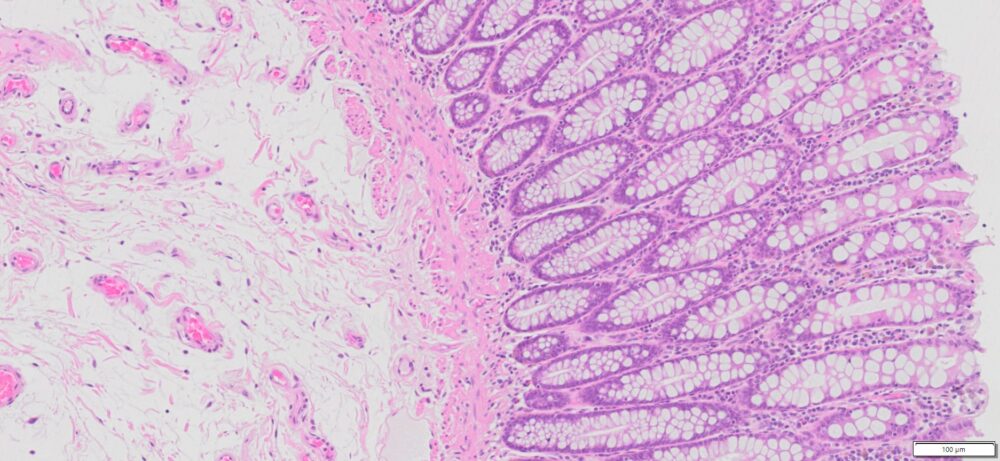

Description

| SKU# | Organ | Pathology Diagnosis | Gender | Age | Grade | TMN | Thickness | IHC Data |

| HuPS-07004A | Human Colon | Normal colon tissue | Male | 71 | — | — | 5μm |

More Image